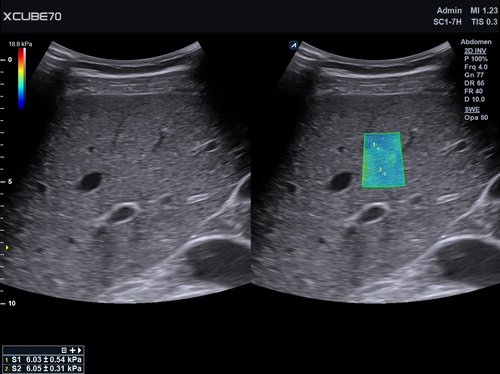

Das X-CUBE 70 bietet modernste Technologien für eine objektive und akkurate Diagnose. Intelligente klinische Module heben das System auf ein neues diagnostisches Niveau. Es erweitert Ihre Fähigkeiten und die Bandbreite Ihrer Möglichkeiten. Dazu gehören Module wie MicroView, point Shear Wave Elastographie (pSWE), oder auch die Kontrastmittelsonographie.

• SC1-7H (1-7 MHz) für Ultraschalluntersuchungen in den Bereichen Abdomen, Geburtshilfe, Gynäkologie, Urologie, Pädiatrie, EM

• SC2-9H (2-9 MHz) für Ultraschalluntersuchungen in den Bereichen Abdomen, Geburtshilfe, Gynäkologie, Urologie, Pädiatrie, EM

• SC2-11H (2-11 MHz) für Ultraschalluntersuchungen in Bereichen Abdomen, Geburtshilfe, Gynäkologie, Urologie, Pädiatrie, EM

• SVC1-8H (1-8 MHz) für Ultraschalluntersuchungen in Bereichen Abdomen, Geburtshilfe, Gynäkologie, Urologie, Pädiatrie, EM